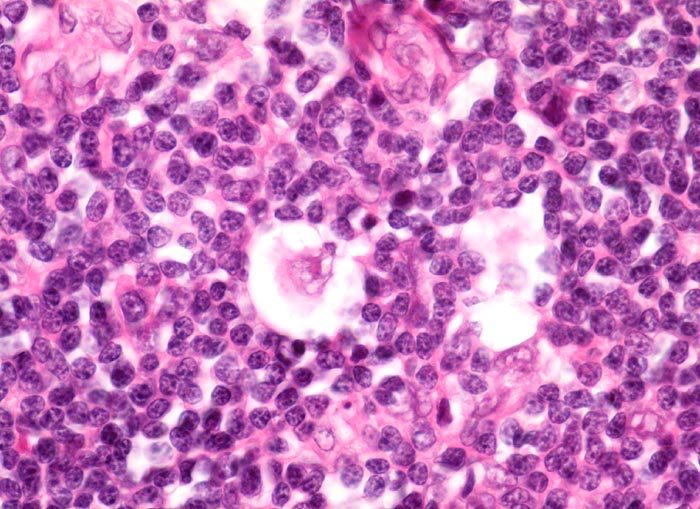

• Reed-Sternbergzelle mit spiegelbildlich angeordneten Kernen mit sehr grossen eosinophilen Nukleolen.

• Einkernige Hodgkinzelle mit prominentem Nukleolus umgeben von einem Retraktionsartefakt (Lakunarzelle).